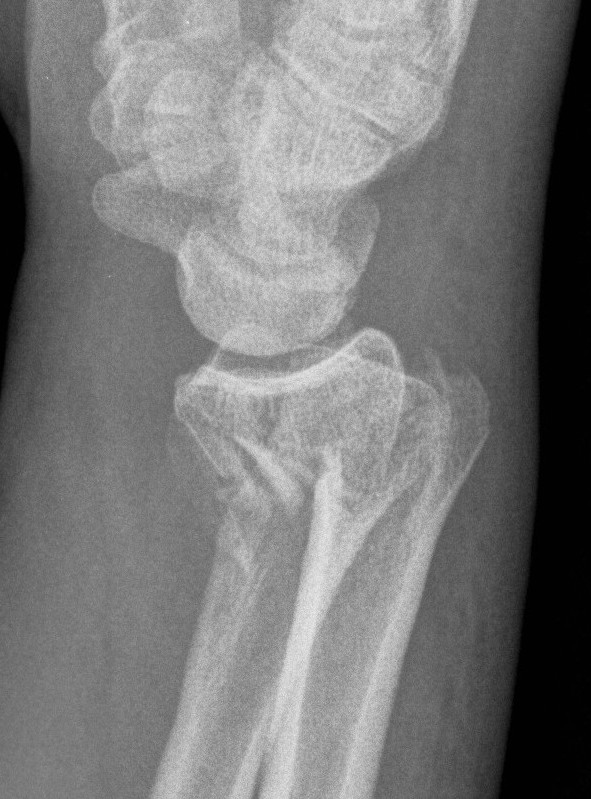

Dorsal / Reverse Barton's

- dorsal intra-articular fragment

Wrist Dorsal BartonsWrist Dorsal Bartons CT